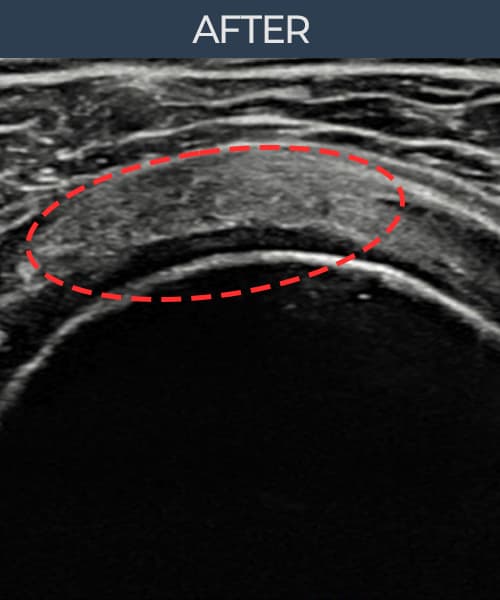

术后

术前超声确认旋转肌腱袖 部分撕裂 + 韧带损伤,冈上肌腱回声不连续伴肌腱缺损(11mm × 6mm (肌腱厚度约58%缺损))。术后超声显示撕裂部位充满再生组织,肌腱连续性恢复,回声模式正常化。

该患者持续肩痛。详细超声检查确认旋转肌腱袖 部分撕裂 + 韧带损伤(缺损:11mm × 6mm (肌腱厚度约58%缺损))。在超声引导下实施非手术缩小缝合术。术后佩戴支具约4-6周,随后进行分阶段康复锻炼。随访超声确认肌腱连续性恢复、结构稳定,患者顺利回归日常生活。